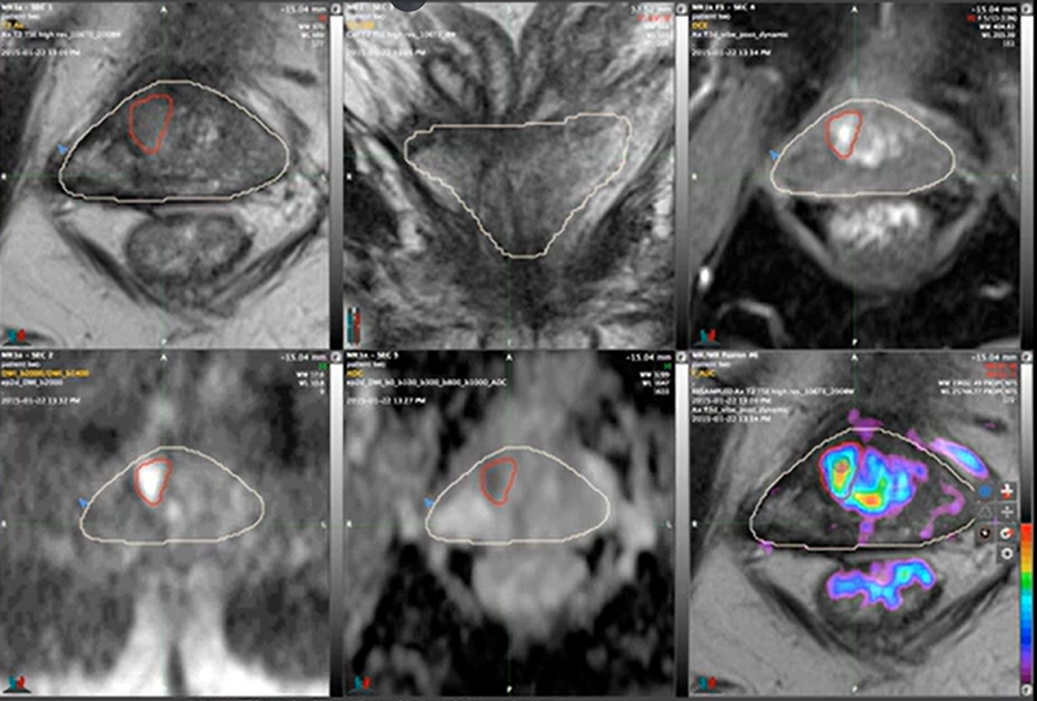

Multiparametric MRI Contouring: Six Views, One Volume

With PCL: Dr. Allen accesses six different MRI sequence views of the same anatomical plane - T2-weighted, ADC, diffusion, vascularity patterns - to contour lesions with millimeter precision.

Six different MRI sequences accessible for precision contouring - T2-weighted, ADC maps, diffusion, vascularity, and more

"The fusion software allows me to view the T2, the dynamically enhanced and the high B value scans, plus the ADC map simultaneously. I can contour the targets using whichever images best show the lesion."